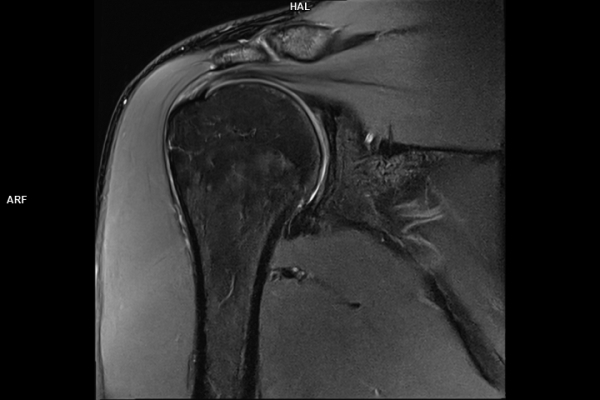

CT Untersuchung Bild

Detailbild MRT